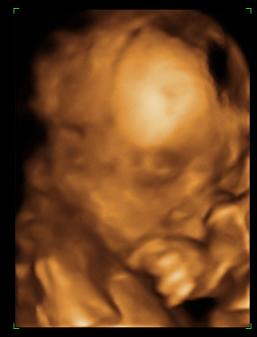

babalak a 22. héten

Dávid